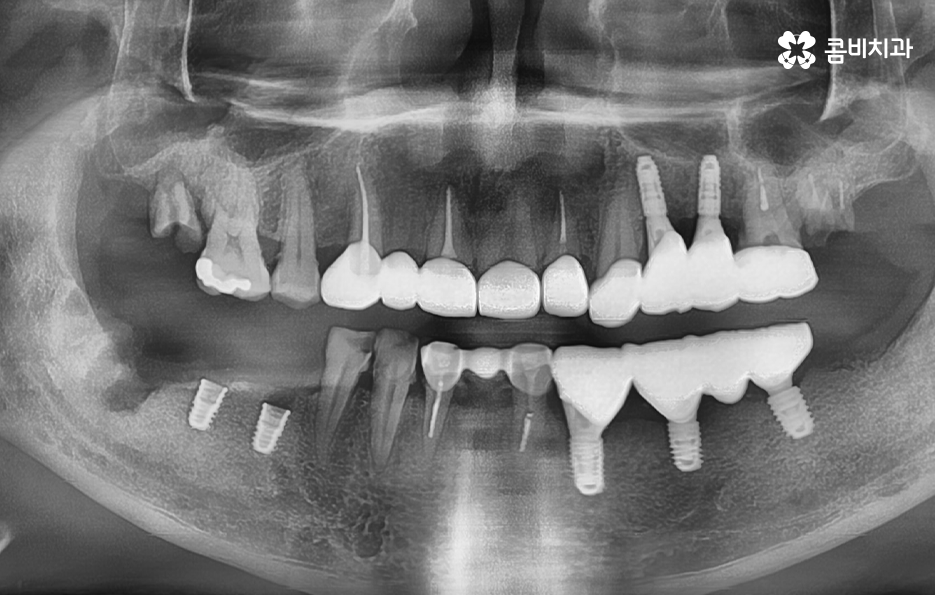

위 사진을 보시면 치아를 이미 잃은지 시간이 지난 상태의 치조골 즉 잇몸 뼈의 상태인 부위도 있고 어떤 치아는 거의 뿌리 부분만 남아 있으며 어떤 치아는 여러개의 보철물이 이어져 있는 상태인 경우도 있는데요

엑스레이 상태만 봐도 치아 저작 기능이 상당히 저하되어 있고 치아 상태가 매우 좋지 않음을 느낄 수 있을 정도인데 사실 임플란트를 필요로 하는 환자분들의 상당 수는 50대 이후부터 노년기에 치아 상실로 인한 임플란트의 필요성을 절실하게 느끼시는 분들이 많고 이미 여러 이유들로 인해 치아도 많이 발치된 경우도 있고 발치를 해야할 상황에서 임플란트를 알아보시는 분들이 많이 있어요

물론 30대 이전에도 치아를 잃게 되시는 분들도 많지만 일반적으로 40,50대 이전에는 충치나 사고로 인해 치아 하나 정도를 잃고 임플란트를 알아보시는 분들이 많고 잇몸이나 전신건강의 상태가 양호하신 분들이 많지만 50대 이후 특히 60대 이후에는 이미 치아를 잃고 시간이 지난 후에 임플란트를 하시는 분들과 치주염으로 인해 여러 치아를 잃게 되는 경우가 많기 때문에 위 엑스레이의 상태처럼 치아 뿐 아니라 잇몸 상태가 이미 안좋은 분들은 흔한 사례라고 할 수 있어요

치아는 발치 후에 서서히 잇몸이 흡수되고 내려 앉게 되는데 이미 치아를 잃고 오랜 시간이 지난 분들의 경우에는 잇몸 뼈가 흡수되어 치조골 상태가 갈수록 얇아지고 내려앉은 상태일 수 있어요

또한 노년기에는 치주염으로 인해 치아를 잃게 되는 경우가 상당히 많은데 치주염으로 인해 잇몸 뼈가 녹은 경우에는 임플란트를 하기에는 잇몸 뼈가 부족하고 골질의 상태가 좋지 않은 경우도 많기 때문에 임플란트 치조골 상태를 건강하게 확보하기 위해 뼈이식을 진행할 수 있어요